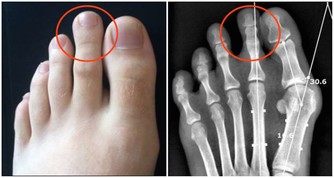

在婦科中,大家可能會知道“帶下病”一說。帶下病這個詞,在中醫裡已經使用幾千年了,因為所有的婦科病都發生在帶脈以下,就連大名鼎鼎的神醫扁鵲,都做過“帶下醫”呢,其實也就是婦科專家。

可不要小瞧帶下病,它是女性健康的晴雨表。有性生活的女性90%都或多或少有帶下病,也就是西醫所謂的各種炎症,包括盆腔炎、宮頸炎、附件炎、子宮內膜炎等等,加之帶脈如果受涼,就會導致痛經、腰酸這些毛病,讓人們苦不堪言。